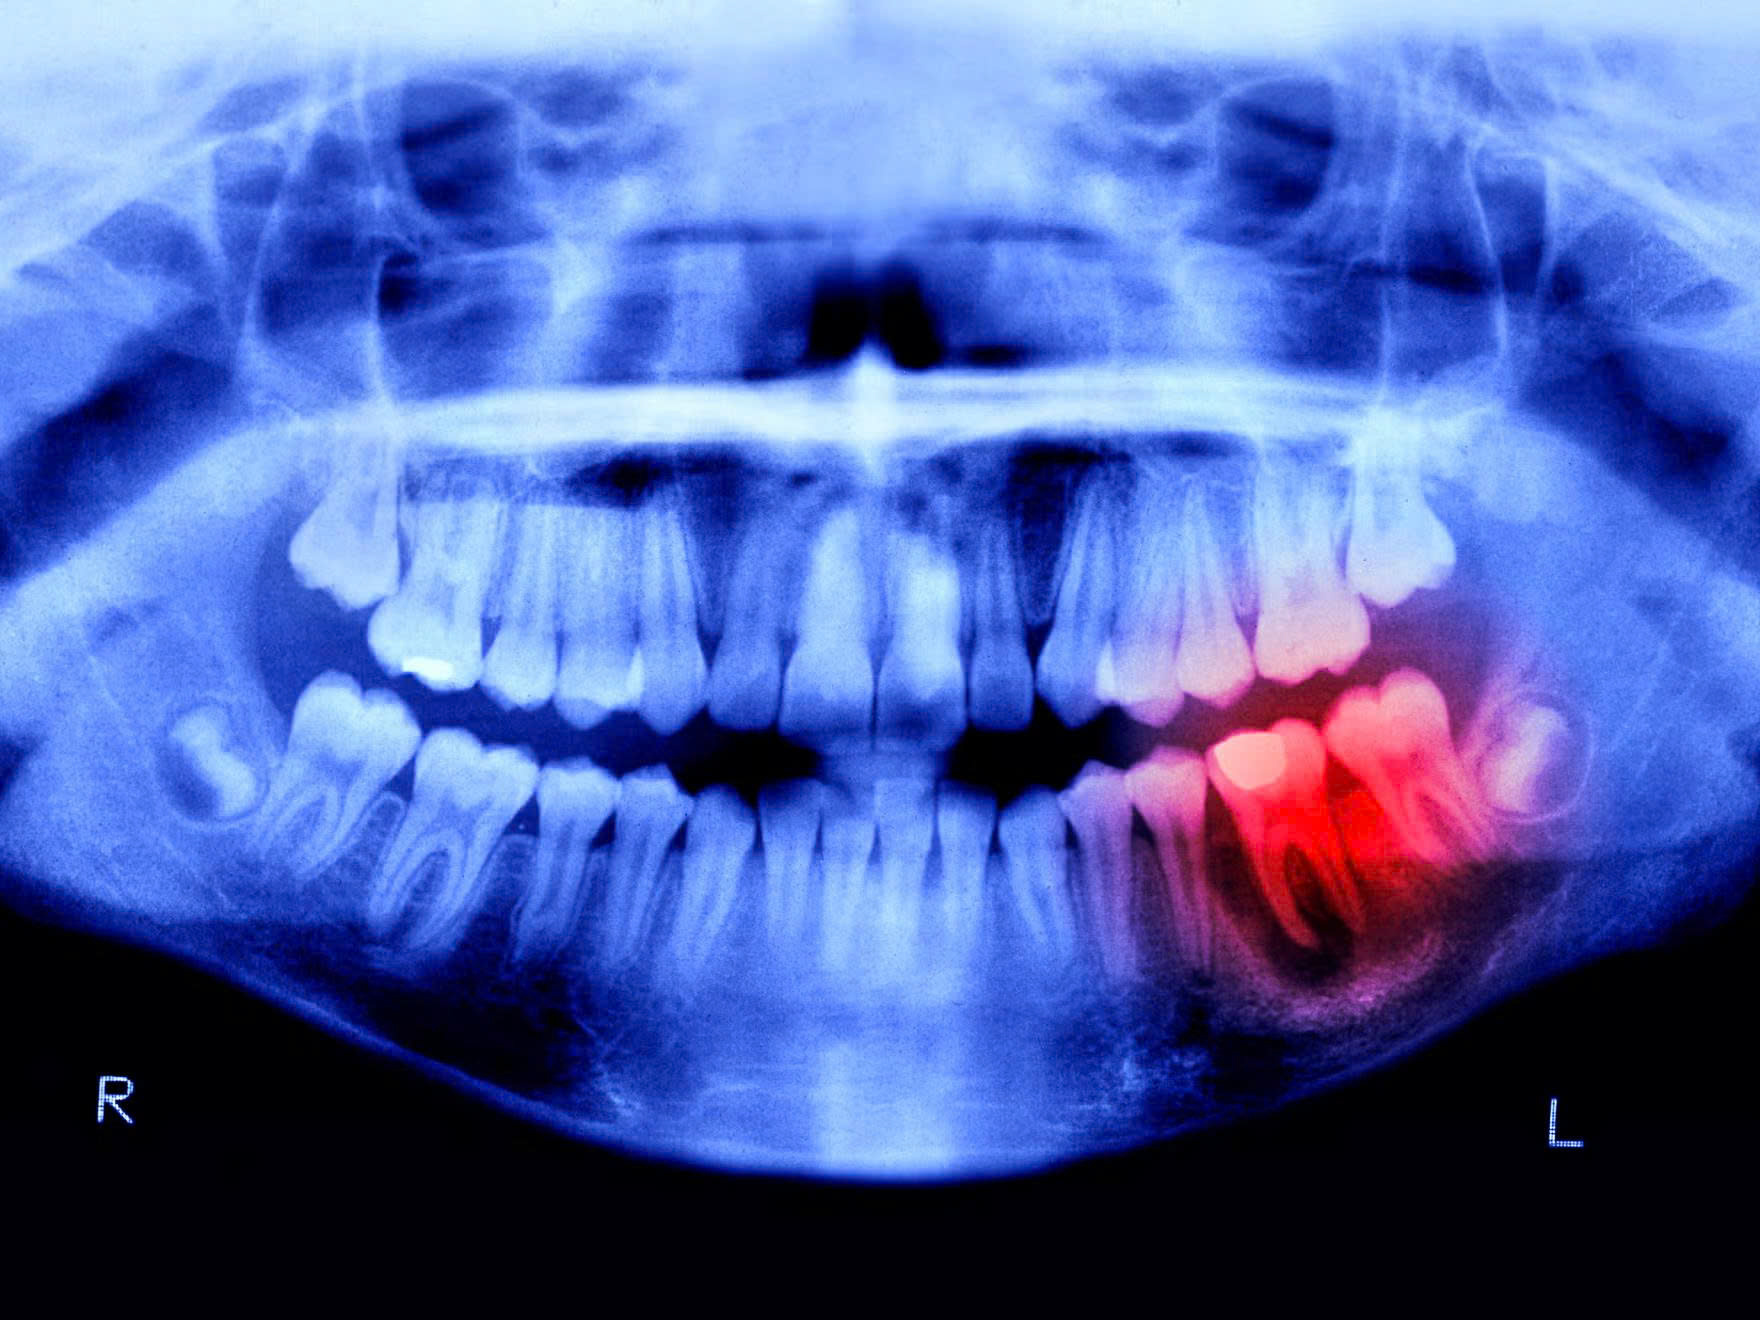

Peter Dazeley//Getty Images